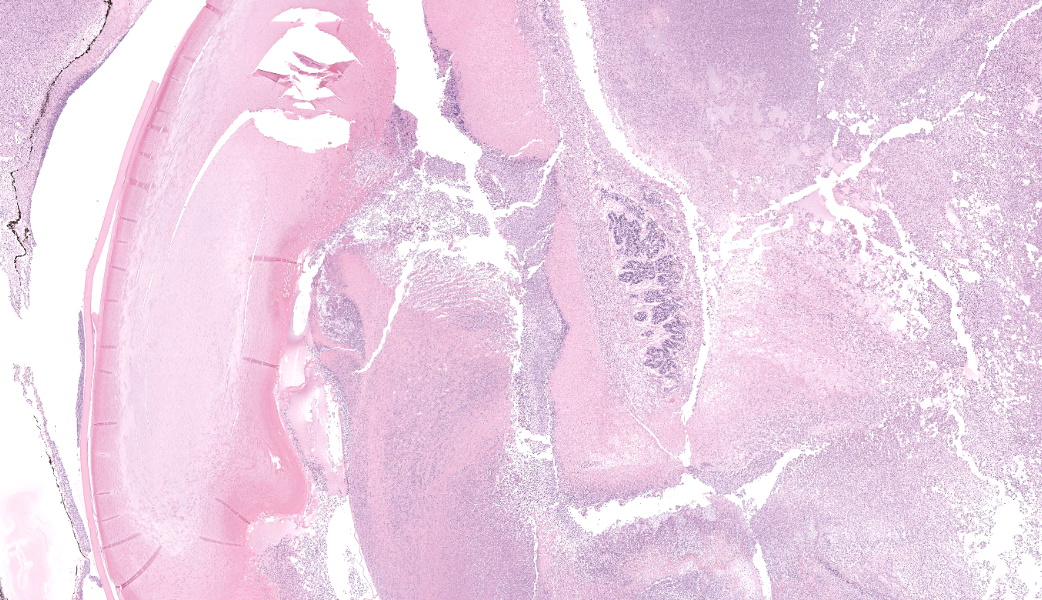

Filling all ocular chambers and coating the surfaces of intraocular structures are vast accumulations of exudate consisting of myriad degenerate and intact neutrophils, many macrophages, abundant amounts of fibrinous to proteinic material, abundant necrotic cellular debris, occasional pools of extravasated erythrocytes, and multifocal colonies of mixed bacteria (rods and coccobacilli). Centrally incorporated into the inflammatory exudates is a ruptured lens which lacks a capsule in many areas and has highly undulating free capsule margins regionally. The lenticular stroma is variably vacuolated with the following features: streaks of pallor, Morgagnian globules, many infiltrating leukocytes (mostly neutrophils), and occasional pockets of similar bacteria. The retina is diffusely detached and largely inapparent apart from remnant segments of atrophied and degenerate retina enmeshed within the exudate. Suppurative to pyogranulomatous inflammatory infiltrates multifocally extend into the iris, ciliary body, choroid, optic nerve which is significantly gliotic with rarefied neuropil, and optic nerve meninges. The iris is displaced anteriorly and multifocally abuts the posterior aspect of the cornea. The anterior chamber is severely narrow, and the drainage angle is collapsed and inapparent. The corneal stroma is moderately to markedly oedematous and contains small to moderate numbers of scattered neutrophils. The anterior corneal epithelium appears attenuated in areas. The sclera is variably thinned with multifocal often perivascular infiltrates of lymphocytes and plasma cells with variable numbers of admixed neutrophils and occasional macrophages. There are increased numbers of perilimbal pigmented cells. A thin to moderately thick layer of oedematous and inflamed granulation tissue regionally lines the mid and posterior scleral margins outside the globe and extends into a bundle of periocular skeletal muscle. In addition to infiltrates of the aforementioned inflammatory cells, the granulation tissue also contains many golden-brown pigmented macrophages (siderophages) which are concentrated at the level of the ciliary body. There is abundant haemorrhage in the retrobulbar loose connective tissue.Contributor's Morphologic Diagnoses:

Endophthalmitis, diffuse, suppurative to pyogranulomatous, severe, with lens rupture, retinal detachment and degeneration/atrophy with intraocular exudation and intralesional mixed bacteria, drainage angle collapse, keratitis, corneal oedema, scleritis and regional periscleral fibrosisContributor's Comment:

Globe: Endophthalmitis, fibrinosuppurative, subacute, diffuse, severe, with lens rupture, synechiae, fibrovascular membranes, retinal detachment and atrophy, and bacterial colonies.JPC Comment:

Talk about a descriptive case that made, for obvious reasons, an excellent sales pitch on why pathology is the best profession! This case provides an excellent opportunity for participants to push themselves on their ocular descriptive abilities. Many thanks to this contributor for a fantastic case! Much like the previous eye case in this conference, there was substantial discussion on ocular pathology. The most informative nuggets from that conversation included utilizing the lens capsule, which is an easily identifiable structure in the eye, to assist with orientation in a busy ocular slide such as this one. The pigmented irideal stroma, as well as the “golden” fibers of the iris, can also be used to help identify structures that might otherwise be difficult to ascertain due to the degree of damage and/or inflammation.This case had beautiful examples of iris bombe (iris pushed forward into the anterior chamber and adhered to the back of the cornea), numerous types of fibrovascular membranes (retrocorneal, preiridial, cyclitic, etc.), and a fantastic phakoclastic panuveitis from lens rupture. The six types of uveitis and their definitions were discussed and included: 1) anterior uveitis (inflammation of the iris and ciliary body), 2) posterior uveitis (inflammation of the ciliary body and choroid), 3) panuveitis (iris, ciliary body, and choroid affected), 4) chorioretinitis (inflammation of the choroid and retina), 5) endophthalmitis (inflammation of uvea, retina, and ocular cavities), and 6) panophthalmitis (all ocular structures are affected, including sclera). Being able to recognize and accurately use these terms as pathologists can provide crucial information to ophthalmologists when it comes to treating these patients.